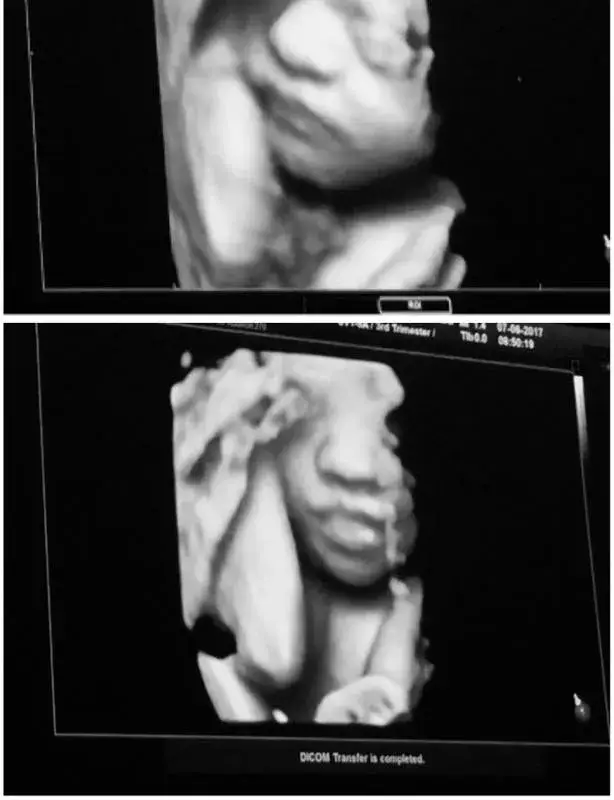

Сървайвърката Янита Янчева показа нероденото си бебе в публичното пространство. Блондинката е вече в 7-ия месец и с нетърпение очаква първата си рожба в Холандия.

Красавицата е била заедно с мъжа си на 4D ехограф, където са останали изключително доволни и впечатлени от визуализацията на бебето им, видя HotArena.

„Това беше един от най-емоционалните моменти в живота ми. Нямаме търпение да те гушнем, малко ангелче“, сподели Янита.